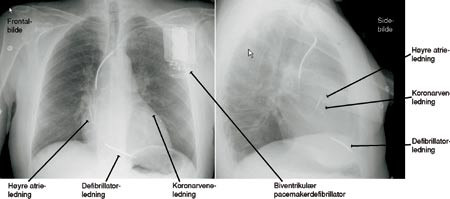

Etter gjennomsnittlig 1,5 år behandlingstid var ni pasienter døde (27 %), og bare tre av disse døde av progrediering av hjertesvikten. Hos fem av de seks som døde plutselig hadde pacemakeren registrert dødelig ventrikulær takyarytmi på dødstidspunktet. Ytterligere en pasient hadde to nærsynkoper, og under begge disse registrerte pacemakeren rask ventrikulær takyarytmi som kunne avleses via pacemakerprogrammereren etterpå. Denne pasienten fikk skiftet pacemakeren til en kombinert biventrikulær pacemakerdefibrillator (fig 3). Tre andre pasienter hadde residiverende episoder med alvorlig ventrikulær takyarytmi, og disse ble behandlet med amiodaron (10).